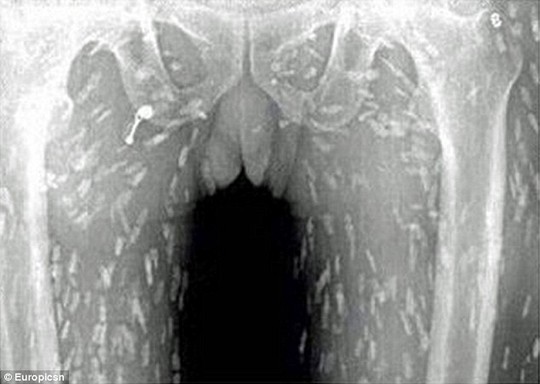

Với biểu hiện đau bụng, ngứa và lúc nào cũng cảm thấy buồn buồn khắp cơ thể, người đàn ông Trung Quốc đã buộc phải đi khám. Kết quả chụp X-quang cho thấy toàn thân bệnh nhân bị nhiễm sán. Thật rùng rợn khi sán có thể sống lúc nhúc khắp trong cơ thể người đàn ông này, và nguyên nhân chính là do ông ta nghiện món sushi.

Sau khi quét toàn bộ cơ thể, các bác sĩ đã nhận được hình ảnh khá kinh dị: Cơ thể bệnh nhân dày đặc giun sán. Người đàn ông cho biết trước đó đã ăn rất nhiều cá sống và các chuyên gia tin rằng món ăn sống từ Nhật (thịt sống, cá sống) có thể là nguyên nhân gây bệnh.